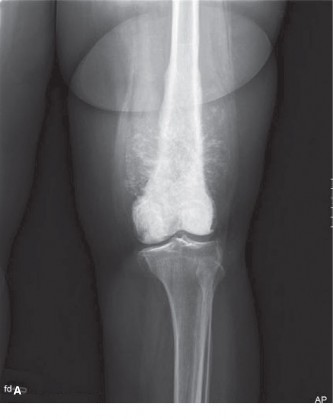

Long Bones

- Diaphyseal Involvement: ES frequently involves the diaphysis or metadiaphysis, often leading to significant cortical destruction and soft tissue extension. The peritumoral edema and reactive zone are extensive, requiring wide margins that may necessitate resection of a substantial segment of the bone.

This image potentially depicts a radiographic representation of a Ewing sarcoma in a long bone, highlighting the typical diaphyseal involvement and periosteal reaction.